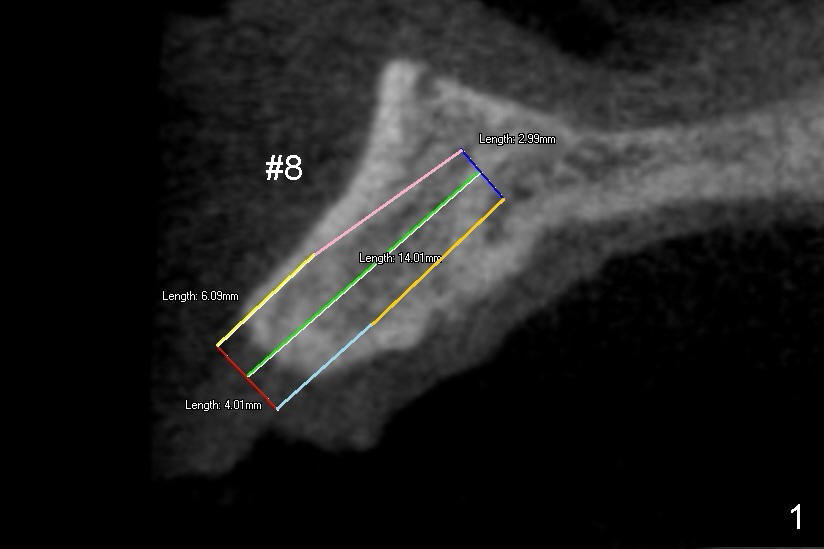

There are two types of implant design for the upper central incisors. The first one is to place implants as large as possible (Fig.1,2), i.e., place the implants in the middle of the alveolar bone, irrespective of the occlusion with the opposing.